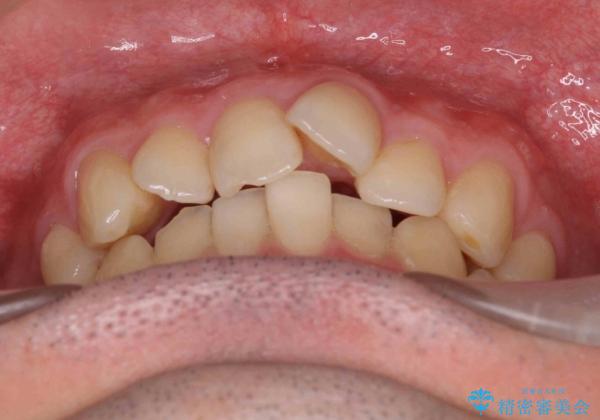

出っ歯と歯のねじれ 非抜歯で 30代男性

- 前歯の並びを気にして来院。

右の歯並びが1本分上が前にずれていました。

本来は抜歯して上の前歯を引っ込めるか、歯を一本分上の奥歯を後ろに下げるやり方が正攻法ですが、

ご本人はそこまでご希望されていませんでした。

奥歯のかみ合わせを特に変えず、前歯の並びを整える治療をおこないました。